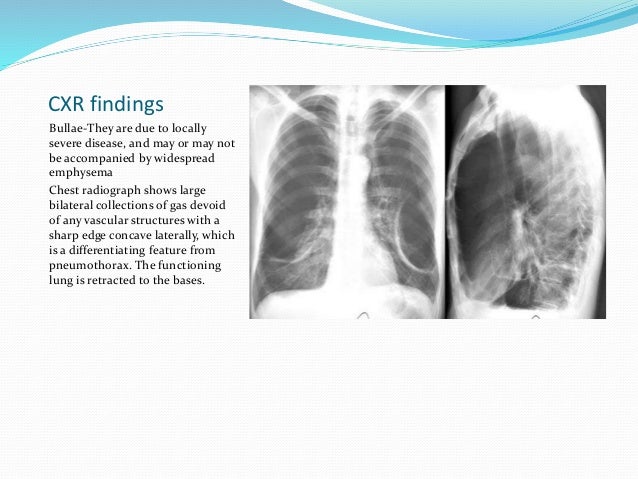

Surgical Treatment for COPD 1 Lung Volume Reduction Surgery involves removing parts of the lung that are most affected by COPD. Removal of lung tissue seems counterintuitive, but it allows the remaining, healthy parts of the lung function more efficiently. 2 Bullectomy involves the removal of bullae from the lungs. Bullae are large air sacs in the lungs that form when a large number of alveoli are destroyed by COPD. These air sacs interfere with breathing.

This means that air is being trapped in your lungs. Other tests include: X-rays: X-rays are generally not useful for detecting early stages of emphysema.